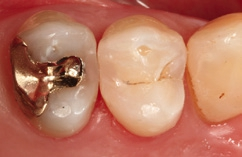

Die Weiterversorgung erfolgte nach adhäsiver Vorbehandlung mit einem approximal eingebrachten 4-mm-Inkrement SDR flow+ (Dentsply Sirona) in der Farbe A3, klassisch überschichtet mit ceram.x universal in der Farbe A3,5. Die Wahl auf ein Bulk-Flow-Komposit approximal fiel aufgrund der optimalen selbstnivellierenden Adhäsion zum Adhäsiv und somit zur Reduktion potenzieller Fehlerquellen in der Schichttechnik, die Wahl zugunsten des eingefärbten SDR flow+ in der Farbe A3 entgegen der transluzenten Universalfarbe U aufgrund der im Approximalraum dunkel erscheinenden Gold-Restauration am Nachbarzahn. Dies ergab in der Vergangenheit bei Verwendung von SDR flow+ U oft ein unschönes „grau-transluzent“ erscheinendes Bild der Kompositrestauration im Approximalraum. Ästhetisch störte dies meist nur bedingt, suggerierte aber immer die latente Möglichkeit einer Approximalkaries. Durch die Verwendung der Farbe A3 bei SDR flow+ war ein derartiges grau-transluzentes Erscheinungsbild nicht mehr gegeben; die Restauration erscheint homogener (Abb. 5). Die Abbildung 6 zeigt die Röntgenkontrollaufnahme nach einem Jahr, die Abbildung 7 die klinische Situation: Der Zahn ist weiterhin vital, symptomlos und beschwerdefrei. Direkte Kompositrestaurationen stellen heute gerade bei vorangegangenen Goldinlay-Kavitäten die suffizienteste Sekundärversorgung dar: Der vorhandene Federrand kann belassen werden und muss nicht in eine plane Stufe einer Keramikrestauration umpräpariert werden.

Im Röntgenbild ist kein Unterschied in der Röntgenopazität zwischen SDR flow+ und ceram.x universal auszumachen, obwohl 2/3 der approximalen Kavitätentiefe von SDR flow+ ausgefüllt wird. Da hinsichtlich ihres Indikationsspektrums direkte Kompositrestaurationen eine ideale Alternative zu Inlayversorgungen darstellen und zudem substanzschonender sowie kosteneffizienter sind, bleibt heute kaum mehr eine wahre Indikation für Inlayversorgungen. Klinisch bewährt hat sich die direkte Kompositversorgung gerade bei dem Austausch kleinerer Goldinlays [13,14].